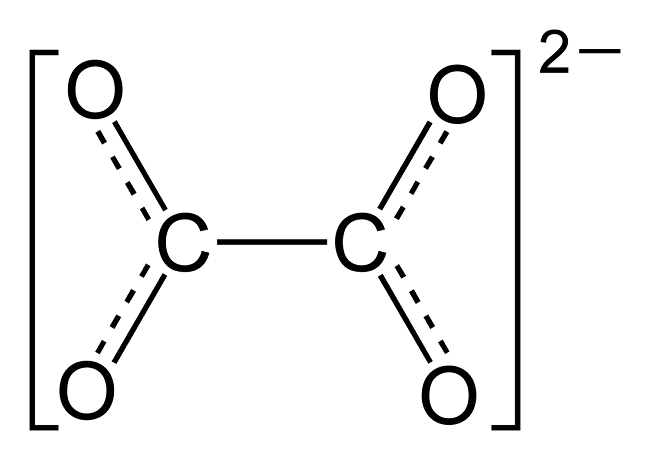

There is a truism in the sociology of occupational knowledge: “If all a doctor has is a hammer, then everything becomes a nail”. All modern medicine relies on overkill dosages of drugs or surgery as the standard of care (Jennifer Daniels, MD, The Lethal Dose, 2013). There are no drugs or surgery that can alleviate the symptoms of poisoning from a natural pesticide found in plant foods but also produced in the liver. With this professional void, treating oxalosis has mainly been left to nutritionists. So, if you ask a nutritionist about oxalates, you will get a predictable answer to reduce oxalates in your diet. This is insufficient because most oxalates are produced by poor metabolism in the liver. Oxalate is a natural pesticide found in plant foods, but also is internally produced mainly from fungus and vitamin C (see How Oxalates Ruin Your Health). Oxalosis manifests as a syndrome of three main symptoms: oxalate crystals in tissues and kidney; histamine, mucous attack in nasal passages; and pseudo-gout mainly from acidity and eating cooked meat.

First, I learned that calcium is needed as a co-valent chemical binder to oxalate before meals to eliminate oxalate through the bowel or oxalic acid through with urine through the kidney. Secondly, I learned that plant foods like spinach, almonds, chocolate, and soy and were loaded with toxic levels of oxalates, a natural pesticide that protects plants from insects, worms, and herbivores. I also learned that high doses of synthetic Vitamin D (10,000 mg/day as a steroid) without Vitamin K2, could also lead to kidney stones and oxalosis. An iron deficiency may come into the picture as discussed below.

My thesis is that internally produced oxalate is systemic and organic. It mainly manifests oxalosis (oxalate poisoning) and is produced in the liver, not solely from dietary oxalate, which can be managed with modest palliative measures. Oxalosis comes from poor elimination in the liver and not entirely from the food we consume. It is an interaction between the two in a feedback loop. I believe that the conventional approach to oxalosis, e.g. reducing the consumption of high oxalate foods, does not significantly reduce internal oxalate production, and thus, is merely palliative.